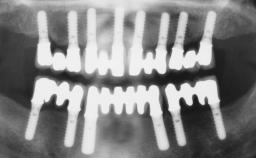

Rehabilitating an Edentulous Maxilla with a Fixed Dental Prosthesis Following Provisional Immediate Loading

This case features the flapless computer-guided placement of 7 bone-level implants, distributed to provide maximal support for the prosthetic framework. A rigid one-piece metallic framework was utilized as an interim restoration to reduce the risk of fracture associated with this prosthetic design. As part of the clinical examination, the SAC Assessment Tool was used, resulting in a surgical and restorative risk classification as “complex”.

# of Implants 7

Guided Surgery Yes